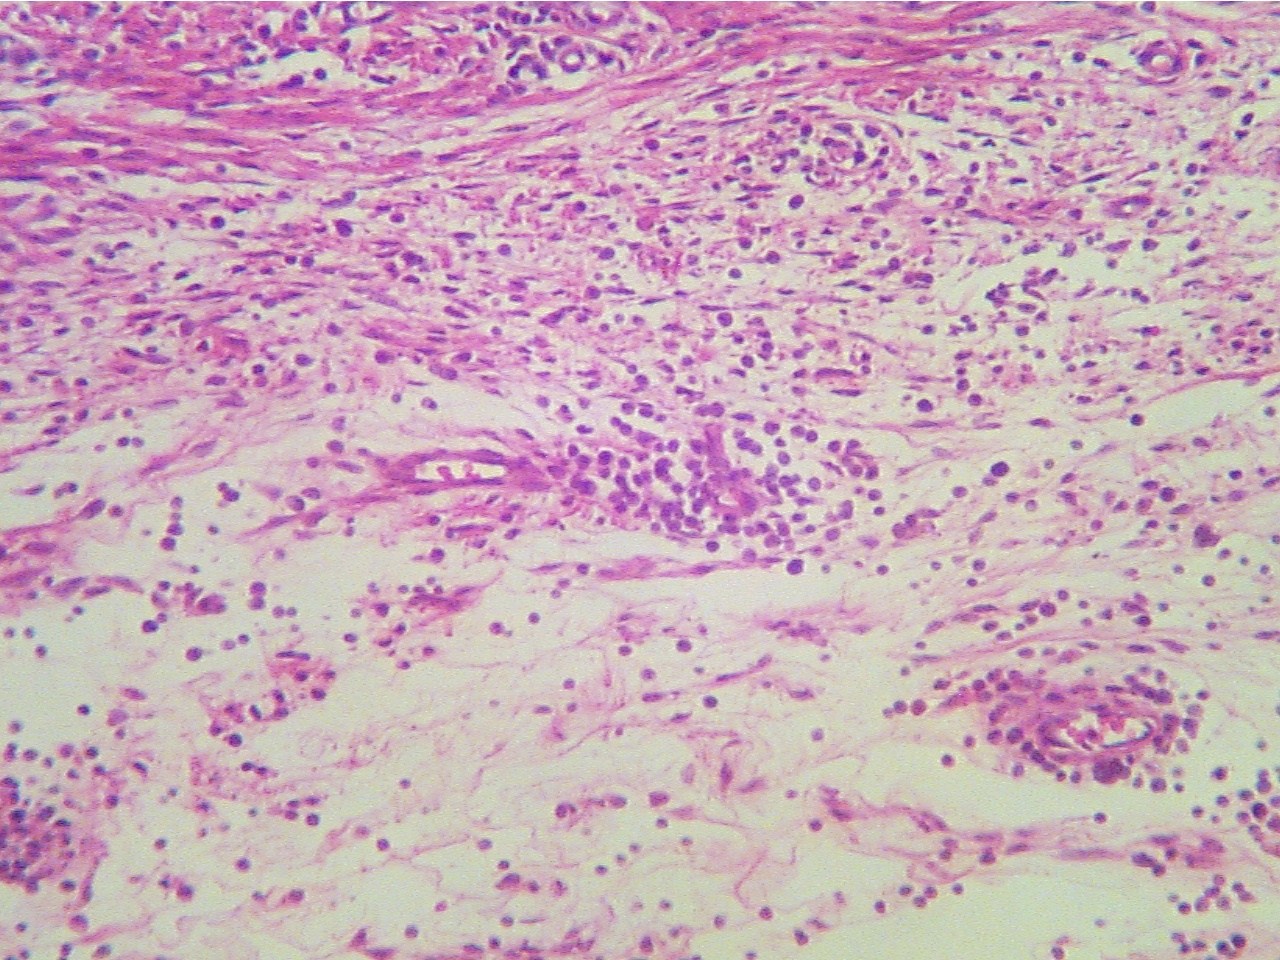

Subcutaneous abscess (100X2.8)

Subcutaneous abscess (400X2.0)

Edge

of dermis (fibers at top), pus (scattered cells

and Pus (scattered inflammatory cells,

tissue debris,

debris in clear liquid at

bottom)

liquid (clear), remains of two capillaries (right)

* What is the name of the

material filling the abscess?